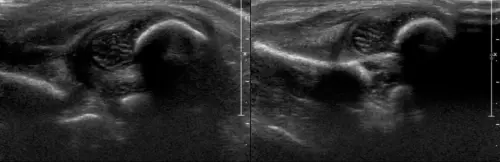

Методика была разработана австрийским ортопедом Рейнхардом Графом и стала международным стандартом в детской ортопедии. Врач оценивает форму вертлужной впадины, положение головки бедра, измеряет специальные углы и классифицирует сустав по типам Графа — от 1А (норма) до 4 (врожденный вывих). Это позволяет не только выявить дисплазию, но и определить степень ее выраженности для выбора правильной тактики лечения. Наиболее информативно УЗИ в первые 4-6 месяцев жизни, далее обследование проводится по показаниям.

Что оценивает врач: форму вертлужной впадины, положение головки бедра, состояние хрящевой губы и два важных угла. Альфа-угол показывает развитие костной крыши впадины (ориентировочная норма больше 60 градусов для возраста 4-12 недель), бета-угол — хрящевой части (ориентировочно меньше 55 градусов). Интерпретацию углов врач проводит с учетом возраста ребенка. По этим углам сустав относят к одному из типов по Графу — от 1А (норма) до 4 (вывих).